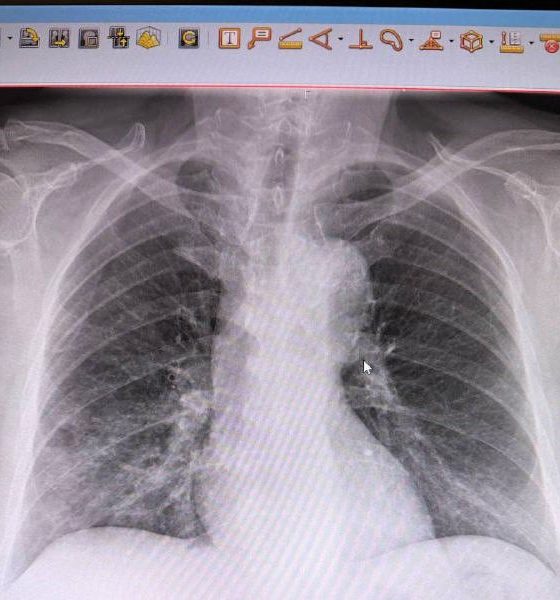

Бригада скорой доставила пациента в в реанимационное отделение Центральной городской больницы с анафилактическим шоком, отеком Квинке и давлением 80/50. Врачи стабилизировали его состояние лишь через сутки. Обследование выявило ещё и пневмонию. Сейчас мужчина переведён в пульмонологическое отделение, его жизни ничего не угрожает.